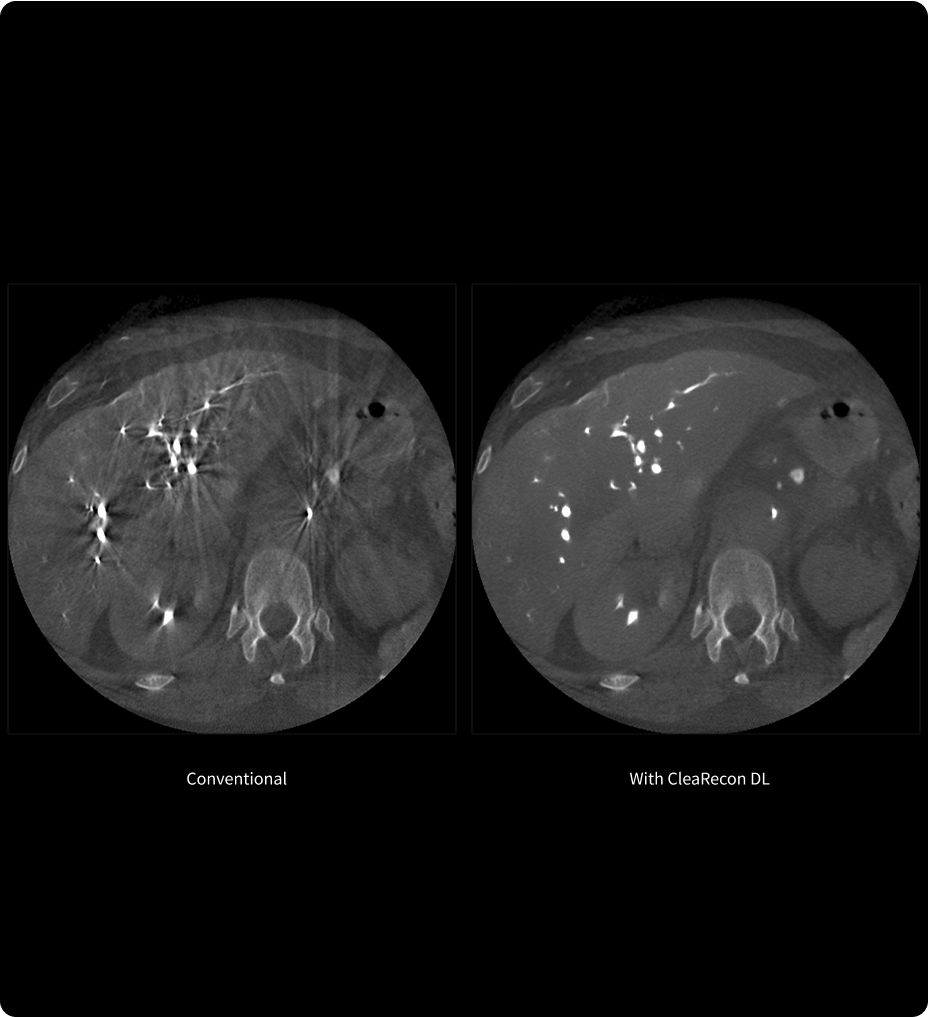

CleaRecon DL3,4

Höhere Bildqualität durch KI

CleaRecon DL ist eine Deep-Learning-Technologie, die zur Verbesserung der Qualität von CBCT-Aufnahmen durch das Entfernen von Artefakten entwickelt wurde. Mit CleaRecon DL können interventionelle Radiologen klarere Aufnahmen erfassen und so das Vertrauen in die Bildinterpretation bei der Analyse von CBCT-Daten stärken.

Zuverlässige Ergebnisse sind für eine genaue Diagnose und eine effektive Behandlungsplanung von entscheidender Bedeutung.

CleaRecon DL: AI-enhanced CBCT image quality for accurate diagnosis and treatment planning